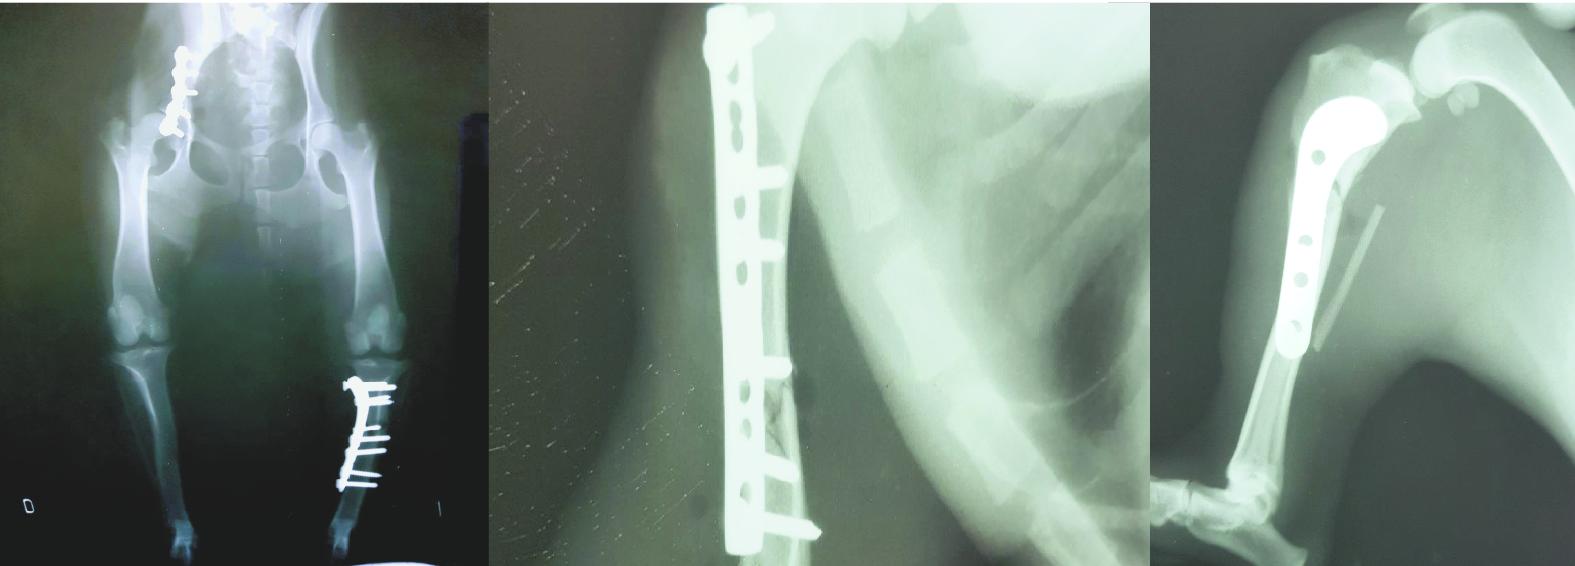

“Atendemos muchos perros politraumatizados. La mayoría son urgencias, como recientemente el caso de Canela, que fue atropellada. Tenía múltiples fracturas en sus patas traseras y delanteras. Vino de Cinco Saltos, rescatada por una señora. Había sido atendida por el colega Martín Gracejo, quien la estabilizó, derivó y llegó acá a tiempo acorde para realizar la operación”.